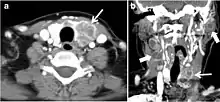

Fig. 8. A 48-year-old male patient post total thyroidectomy with PTC recurrence. a Transverse greyscale ultrasound of the neck demonstrates a left thyroid bed heterogeneous, predominantly hypoechoic irregular lesion with calcifications (white arrow). b A spot image of iodine 123 total body scan of the neck demonstrate a focus of abnormal radiotracer uptake at the left thyroid bed (Black arrows) between the annotated markers. c Enhanced axial CT scan of the neck demonstrates an enhancing large left thyroid bed mass (white arrow) with no calcifications. The lesion exerts a mass effect on the oesophagus (black arrow) and is inseparable from the trachea.[1]